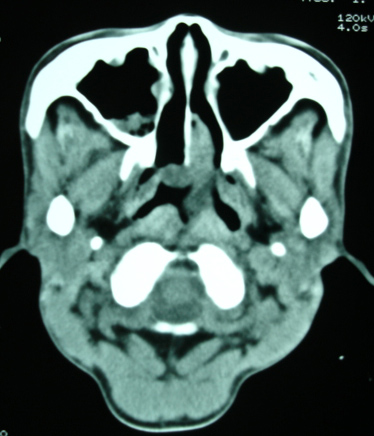

以下是引用bmw011在2009-4-23 13:23:00的发言:[br]考虑鼻息肉,上颌窦、筛窦炎

以下是引用syfszcw在2009-4-23 13:21:00的发言:[br]双侧上颌窦 筛窦慢性炎症,鼻息肉 会厌ca[br][br][本贴已被 syfszcw 于 2009-4-23 13:36:46 修改过]

以下是引用随光逐影在2009-4-23 19:35:00的发言:[br]1)鼻咽、口咽、左侧鼻腔及右侧鼻后孔处新生物,考虑息肉可能性大。2)双侧上颌窦及双侧筛窦炎症,不排除双侧上颌窦内息肉可能。